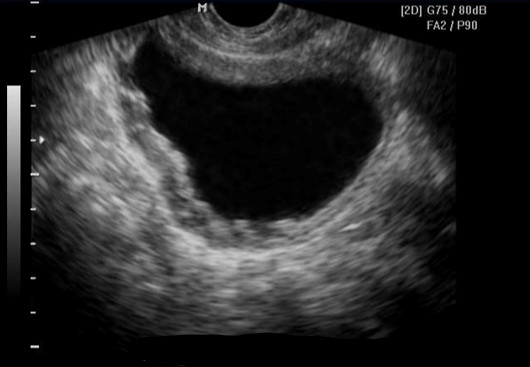

Name this pathology that presents as a spherical structure that does not communicate with the renal collecting system.

What is a parapelvic cyst?